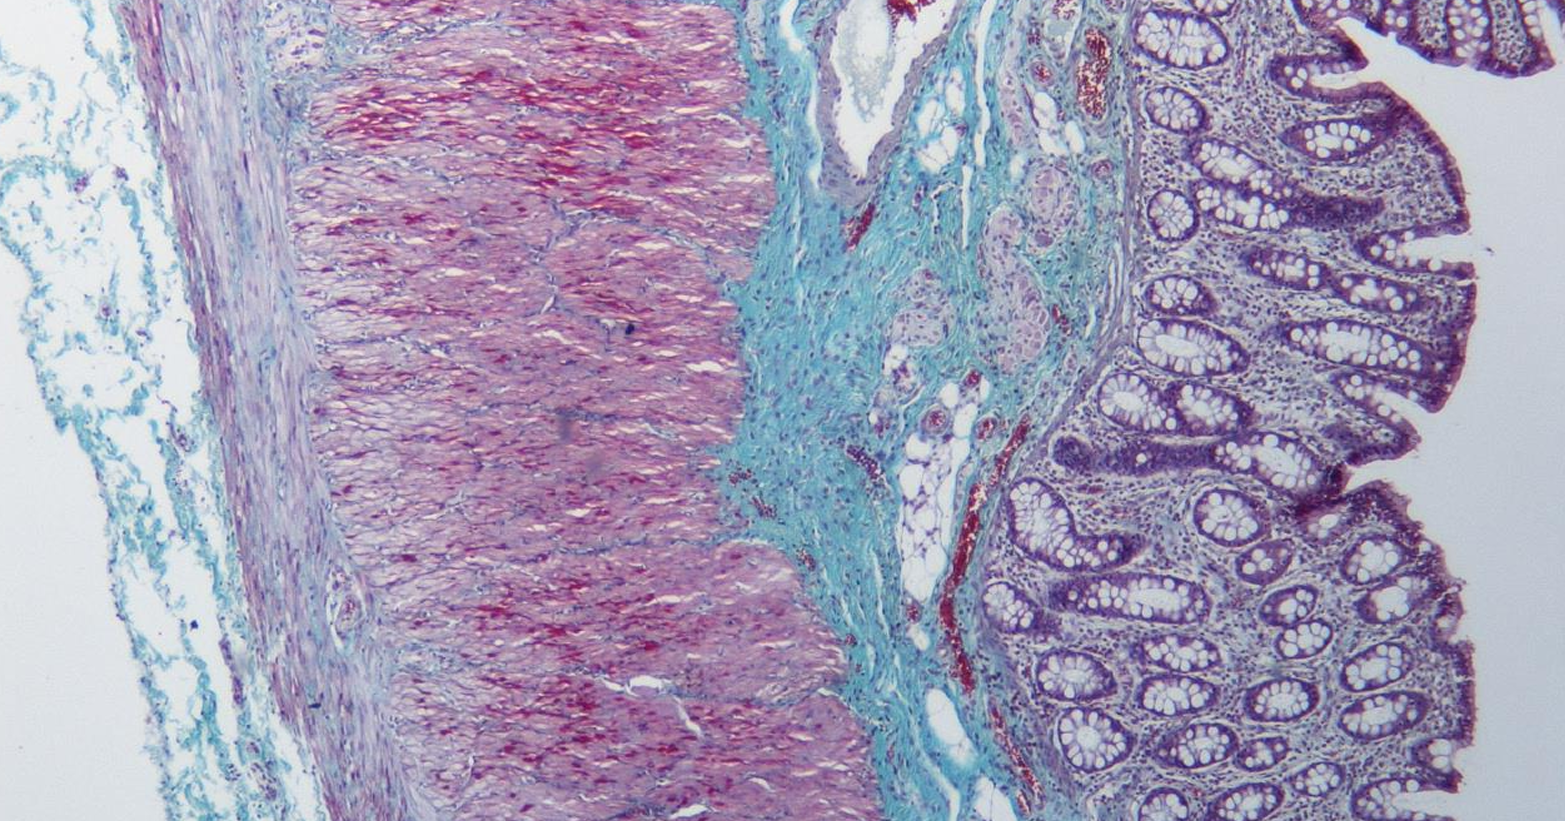

intestino grueso es la parte final del sistema digestivo, encargada de absorber agua y electrolitos, además de formar y eliminar las heces.